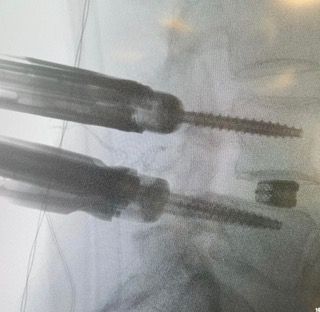

Starszy Asystent w Klinicznym Oddziale Neurochirurgicznym oraz Poradni Neurochirurgii Wojewódzkiego Szpitala Specjalistycznego im. św. Barbary nr 5 w Sosnowcu. Konsultant Kliniki Neurologii Szpitala Klinicznego nr 1 w Zabrzu. Absolwent Wydziału Lekarskiego Śląskiego Uniwersytetu Medycznego w Zabrzu. Staż podyplomowy odbył w latach 2010-2011 w Oddziale Neurochirurgii WSS nr 4 w Bytomiu. W 2018r. złożył egzamin specjalizacyjny po zakończeniu szkolenia w ramach rezydentury w WCM Opole. W 2019 roku uzyskał stopień doktora nauk medycznych. Specjalizuje się w kompleksowym leczeniu schorzeń kręgosłupa (dyskopatia, stenoza kanału kręgowego, kręgozmyk) oraz neuroonkologii. Szczególny zakres działań medycznych to nowoczesne, małoinwazyjne operacje kręgosłupa z wykorzystaniem technik endoskopowych (mikrodiscektomia - implanty rozprężalne), przezskórnych stabilizacji oraz mikrochirurgicznych dekompresji. Wykonuje procedury iniekcyjne; discoGEL, GelSTIX, kriolezje oraz blokady przeciwbólowe kręgosłupa odcinka szyjnego, lędźwiowo-krzyżowego a także stawów krzyżowo-biodrowych, które odgrywają istotną rolę w procesie diagnostyczno-leczniczym wielu zespołów bólowych. Na co dzień przeprowadza operacje w ramach kontraktu z NFZ. Członek Polskiego Towarzystwa Neurochirurgów oraz Polskiego Towarzystwa Chirurgii Kręgosłupa. Uczestnik wielu krajowych i zagranicznych kursów neurochirurgicznych, m.in. w Czechach, Słowacji, Niemczech, Włoszech, Danii, Austrii, Szwajcarii i USA. Autor licznych publikacji naukowych.

Zdjęcia i filmy